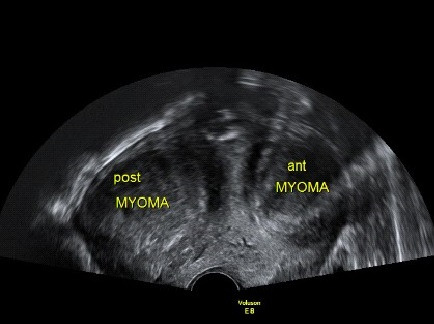

임신을 준비하는 여성들의 초음파 검사에서 관찰되는 영상입니다.

2. 자궁근종 (Myoma uteri)

자궁근종이 있는지, 자궁 용종이 있는지, 난소에 혹이 있는지 확인할 수 있는 간편하면서도 정확도가 높은 검사입니다. 비용은 병원마다 천차만별이오니 꼭 미리 확인하고 가시기 바랍니다. 자궁근종, 자궁 용종, 난소에 자궁내막종의 여부에 따라 난임에 대한 접근방법이 바뀔 수 있어 필수적으로 시행하는 검사입니다.